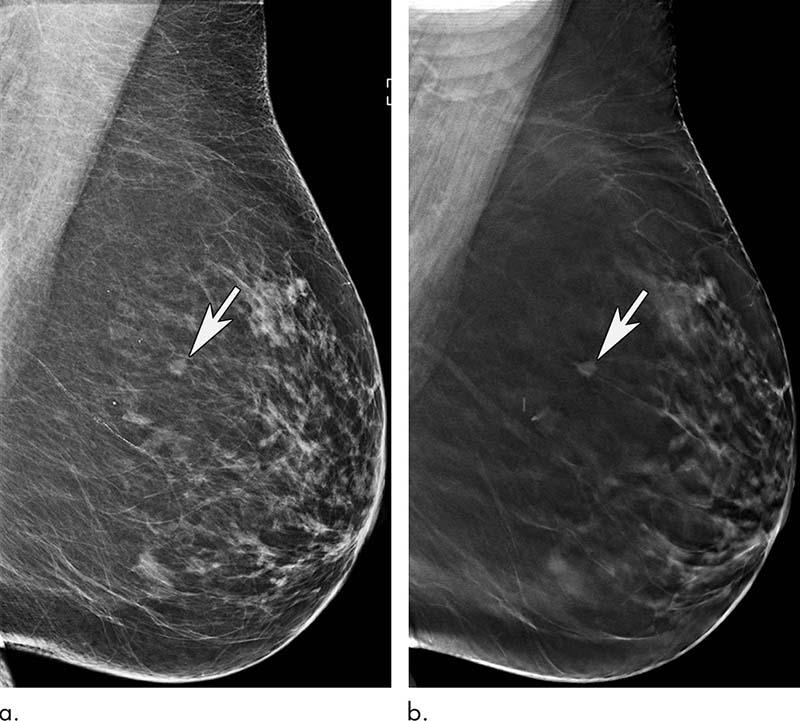

Mammography remains an effective method for breast cancer screening in women ages 65 and older, with the addition of tomosynthesis improving screening performances even more, according to a study published in Radiology.

In the new study, researchers at Massachusetts General Hospital (MGH) compared screening mammograms from more than 15,000 women (mean age 72.7 years) who underwent DM with those of more than 20,000 women (mean age 72.1 years) who underwent tomosynthesis. Both approaches were highly effective at detecting cancer, but tomosynthesis had some advantages over the 2D approach, including a reduction in false-positive examinations. Tomosynthesis also had a higher positive predictive value and higher specificity than DM.

“We’ve shown that screening mammography performs well in older women, with high cancer detection rates and low false-positives, and that tomosynthesis leads to even better performance than conventional 2D mammography,” said study lead author Manisha Bahl, MD, MPH, radiologist at MGH and assistant professor of radiology at Harvard Medical School. “For example, the abnormal interpretation rate, which is the percentage of women who are called back for additional imaging after a screening mammogram, is lower with tomosynthesis than with conventional 2D mammography. We also found that fewer cancers detected with tomosynthesis were lymph node-positive, suggesting that we are detecting cancers at an earlier stage. Detecting breast cancers at an early stage is the goal of screening mammography.”